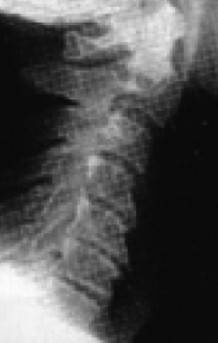

Рис. 12. Правильный физиологический изгиб А=А1 (слева). Гиперлордоз шейного отдела – B больше B1 (справа)

Причем, опять же, рост этого горбика она объясняет исключительно «солями» – остеохондрозом – и не связывает с изменившейся статикой своего позвоночника. В норме позвоночник, как известно, не должен быть прямым, как палка, а иметь физиологические изгибы. В частности, шейный отдел, состоящий из 7 позвонков, в норме должен быть чуть прогнутым внутрь (рис. 13).

Рис. 13. Нормальная статика шейного отдела

Рис. 13а. Спрямление шейного отдела

Рис. 13б. Гиперлордоз шейного отдела